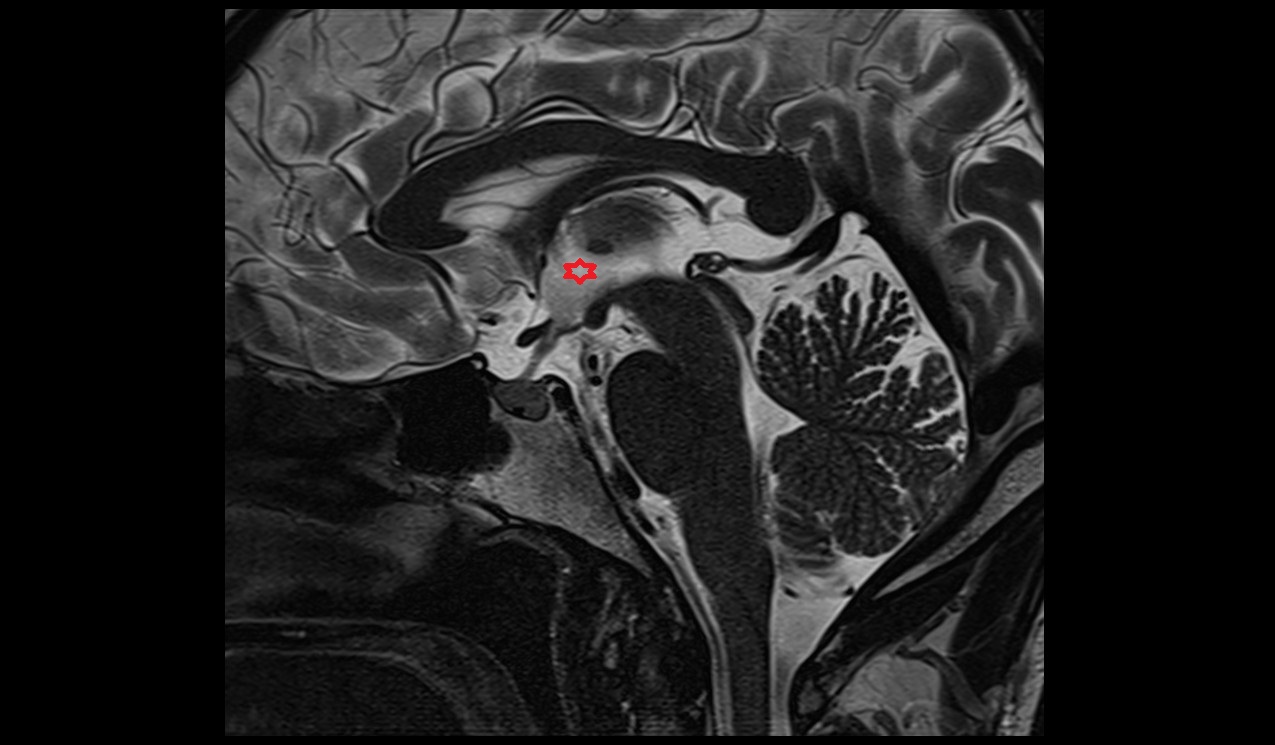

- Aqueduct of midbrain (Sylvian Aqueduct)

- Cerebral aqueduct